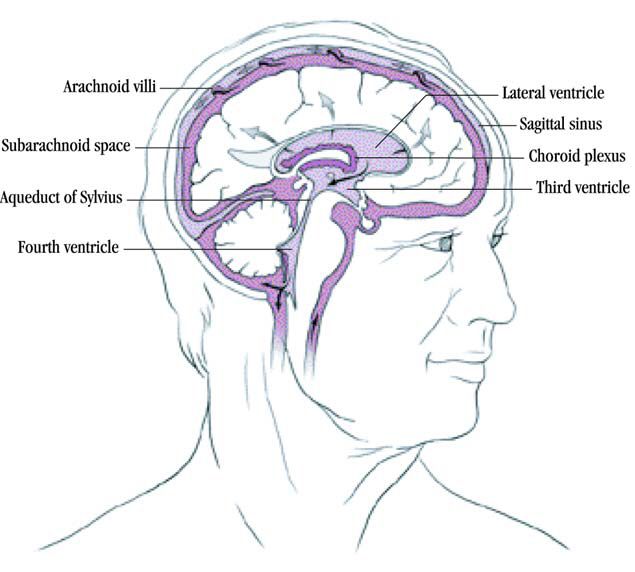

Hydrocephalus

Choroid Plexus – The Definitive Guide | Biology Dictionary